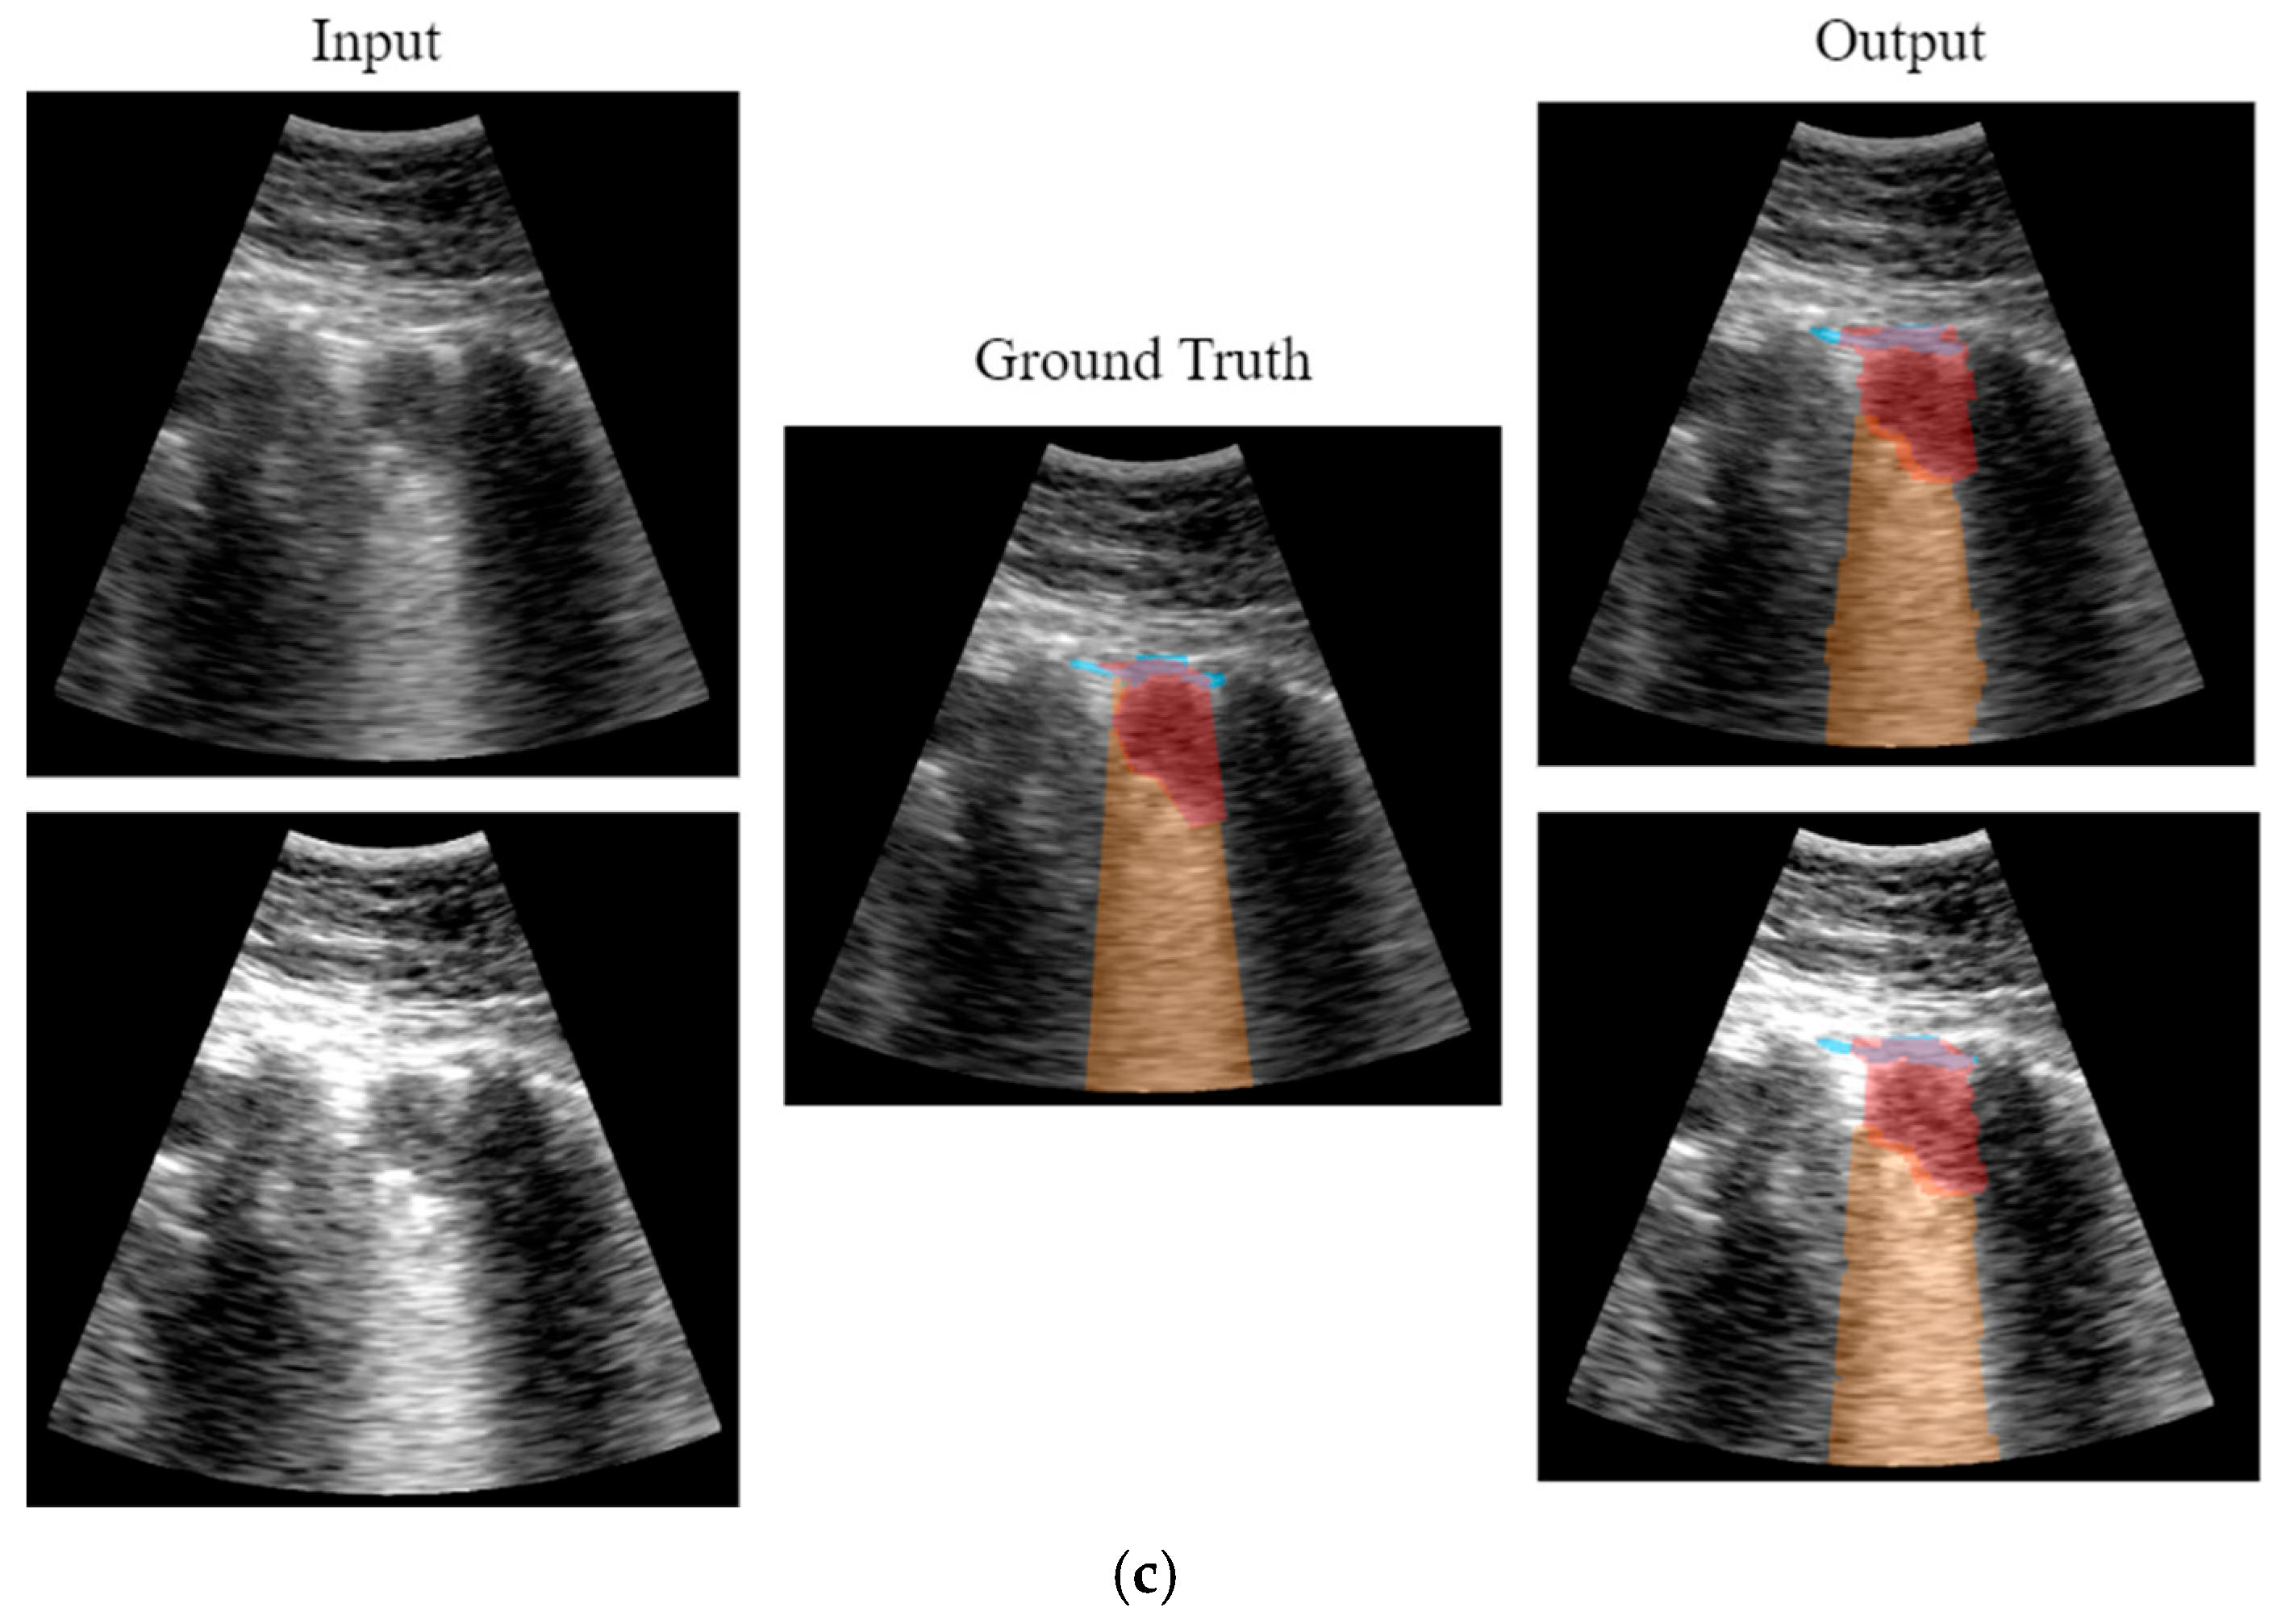

The approach followed in this work was that, given a video labeled by the expert as containing a consolidation, a key frame where this consolidation is seen is first identified. Then, it is manually delineated using a custom developed interactive tool (Figure 9). Finally, an optical flow algorithm [27,28] tracks the movement of the consolidation in the subsequent frames, automatically generating the ground truth masks for the entire video. The optical flow algorithm is based on the principle of selecting a set of reference points and tracking them through the video. This algorithm is particularly suited for ultrasound images because the texture generated by the image speckle can be used for this purpose. The implemented application requests frame-by-frame validation from the user to ensure correct labelling. In case the algorithm fails in the detection, the points of interest will be re-selected again.

Figure 9.

(a) Tool developed for consolidation annotation; (b) tracking secuence over four consecutive frames.